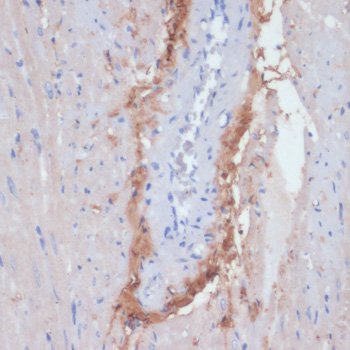

Immunohistochemistry of paraffin-embedded human liver cancer using COL1A1 at dilution of 1:200 (40x lens).

Immunohistochemistry of paraffin-embedded human lung cancer using COL1A1 at dilution of 1:200 (40x lens).

Immunohistochemistry of paraffin-embedded human placenta using COL1A1 at dilution of 1:200 (40x lens).

Immunohistochemistry of paraffin-embedded mouse lung using COL1A1 at dilution of 1:200 (40x lens).

Immunohistochemistry of paraffin-embedded mouse spleen using COL1A1 at dilution of 1:200 (40x lens).

Immunohistochemistry of paraffin-embedded Rat heart using COL1A1 at dilution of 1:200 (40x lens).

Immunohistochemistry of paraffin-embedded rat ovary using COL1A1 at dilution of 1:200 (40x lens).